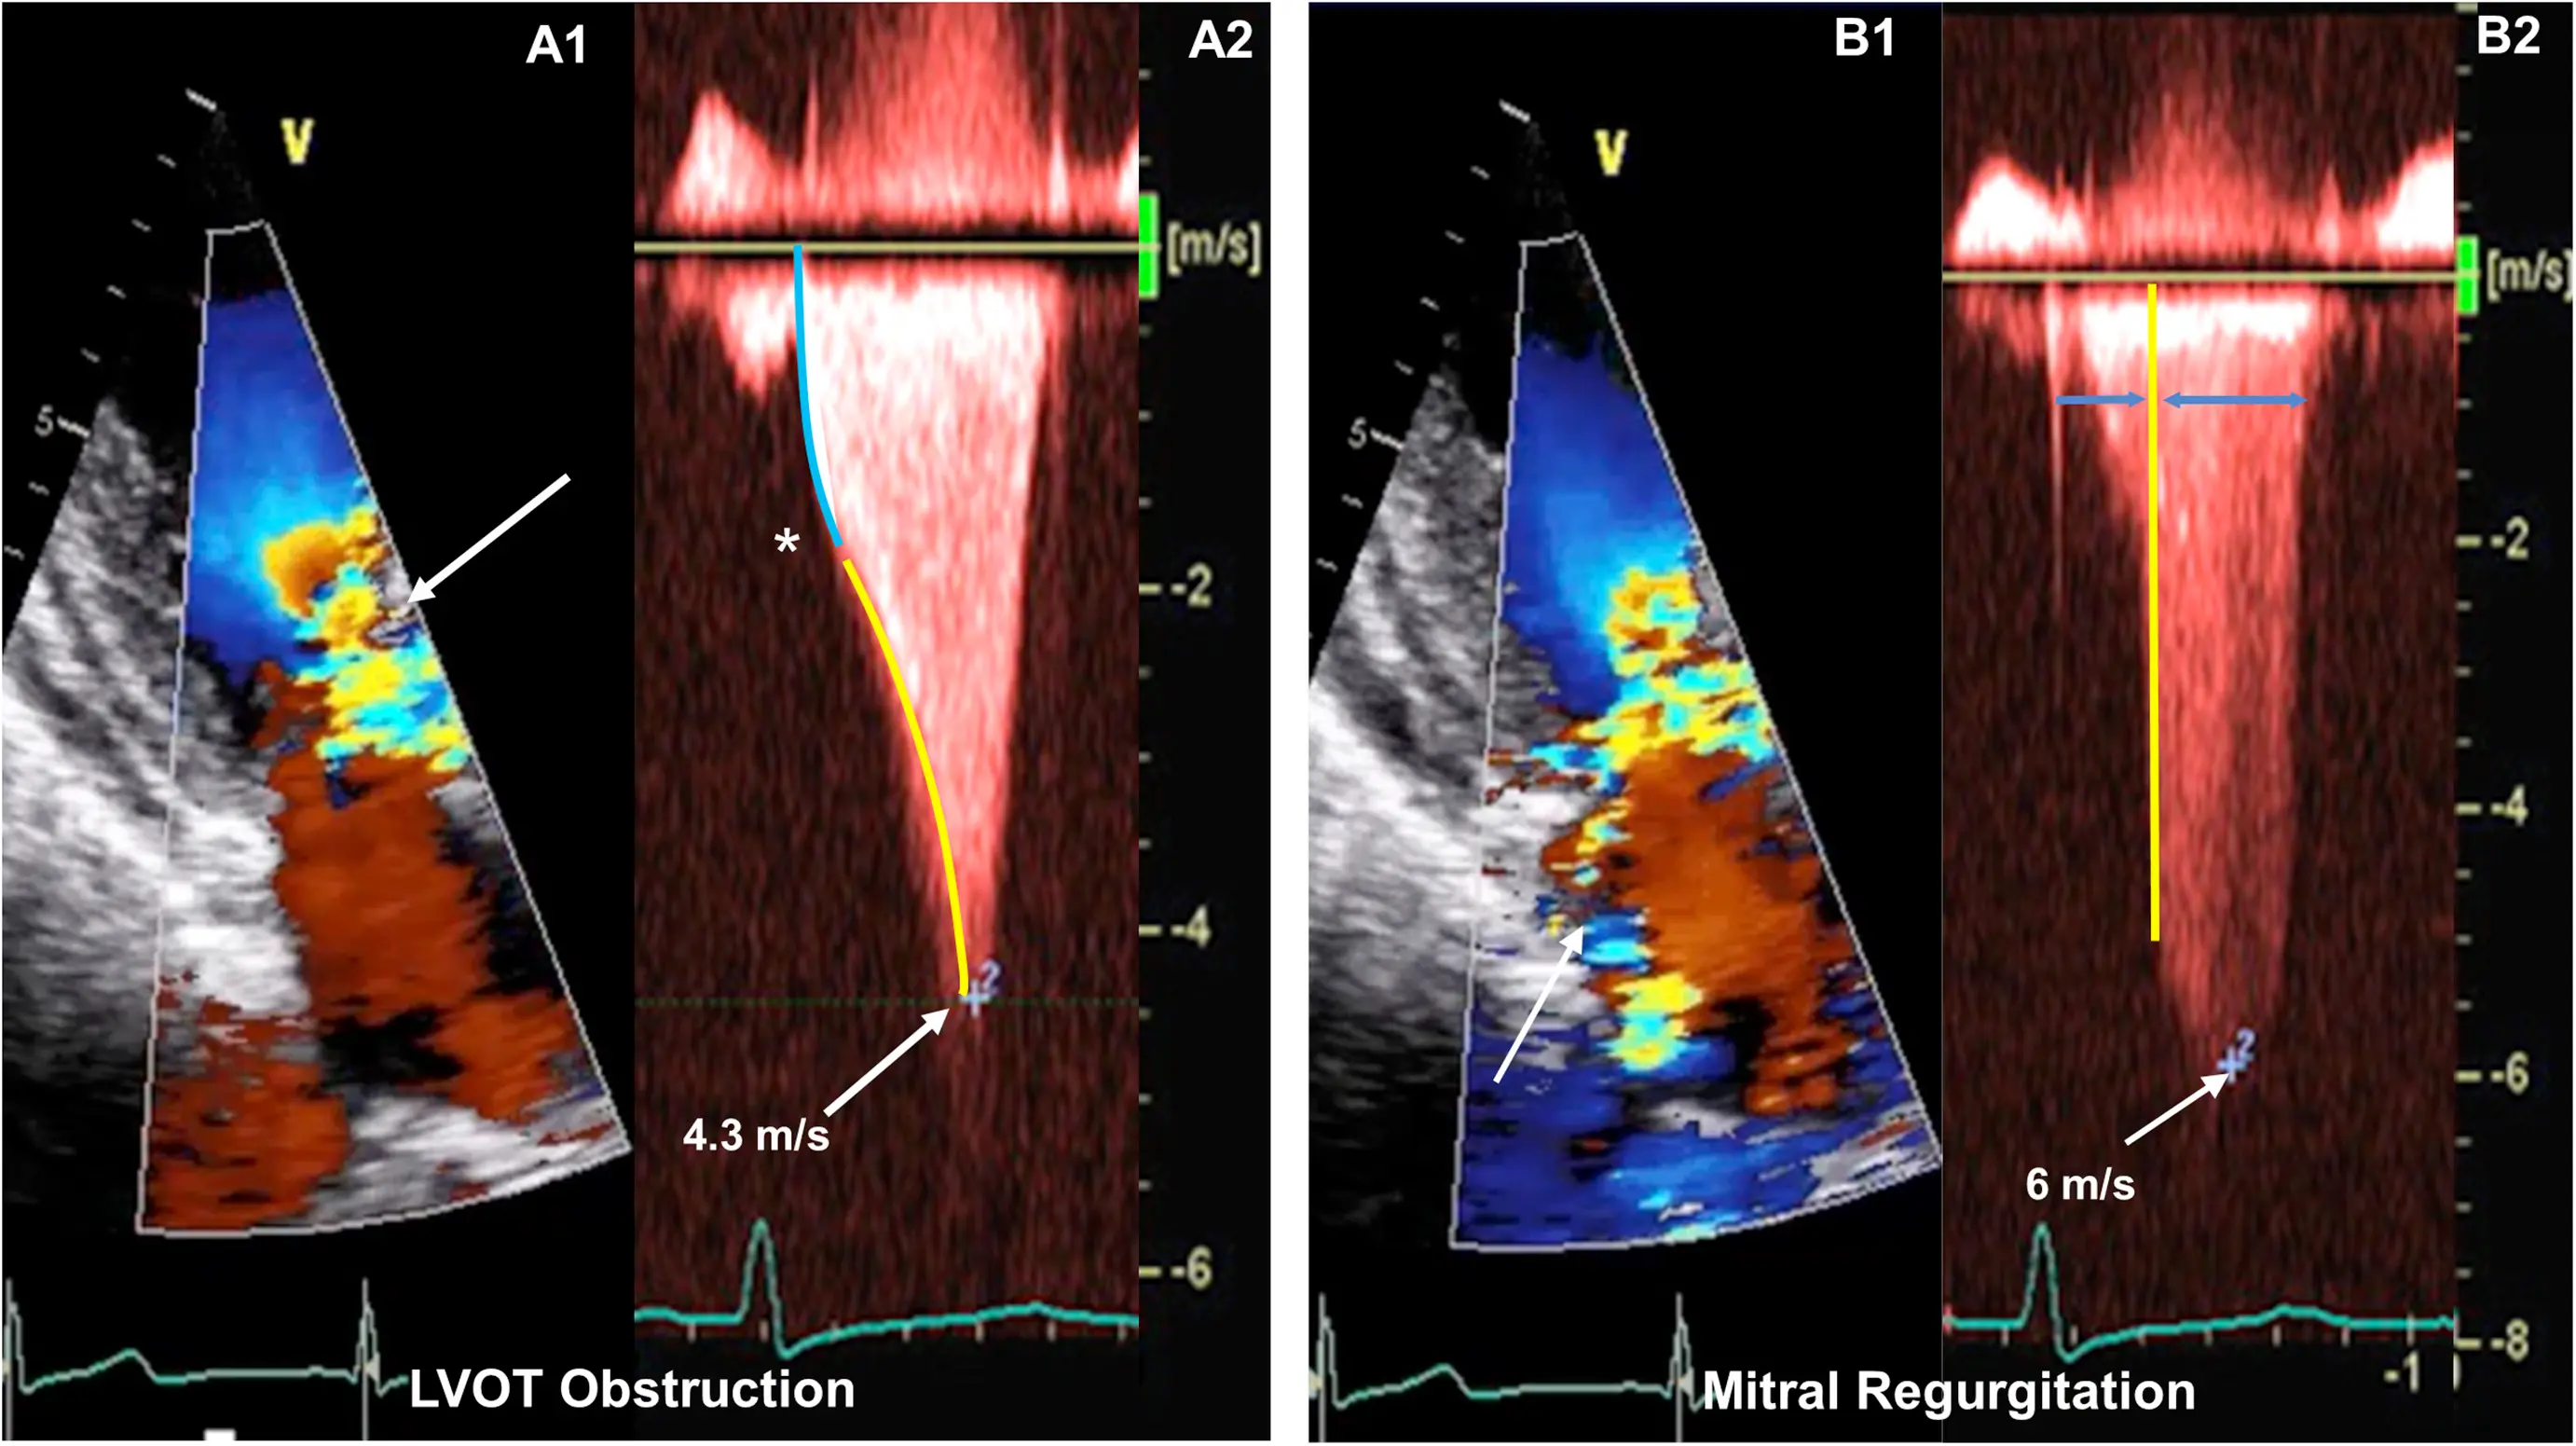

M-mode

- Temporal resolution of M-mode → the duration of SAM where it is in contact with the septum correlates w/ severity of LVOT obstruction

- M-mode in the parasternal long-axis view may assess for midsystolic notching of the aortic valve, reflecting very rapid ejection of LV stroke volume in early systole followed by attenuation of stroke volume in the obstructive phase.